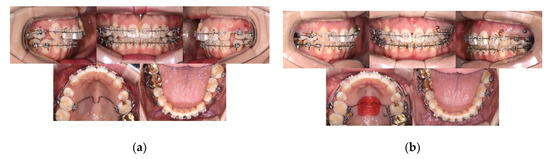

Case Report